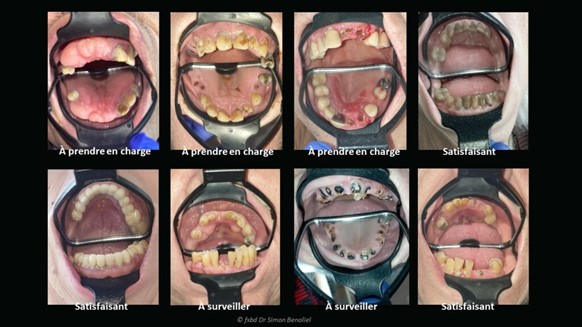

Matériel et Méthodes : L’étude est une intervention multicentrique prospective impliquant 76 résidents de maisons de repos à Bruxelles. Les examens buccaux incluaient des indicateurs tels que le nombre de dents présentes, absentes, cariées, le nombre de racines et l’indice de plaque. Des photos des arcades dentaires ont été prises à l’aide de l’Odontoscope® pour une évaluation à distance. Les résultats de ces examens distanciels ont été comparés à ceux des examens en présentiel.

Discussion : Les examens buccaux distanciels montrent une corrélation significative avec les examens en présentiel pour plusieurs indicateurs de santé buccale, démontrant ainsi la fiabilité de l’Odontoscope® pour certaines évaluations. Cependant, la méthode présente des limites pour le diagnostic des caries dentaires, nécessitant encore l’examen clinique direct pour une évaluation précise.

L’Odontoscope reste donc un instrument qui facilite l’examen bucco-dentaire visuel que pourrait réaliser des personnels de soins non professionnels de la dentisterie. Ces personnels devront être formés à l’utilisation et à la manipulation de l’Odontoscope, afin d’optimiser les résultats photographiques obtenus dans le cadre d’une demande de téléexpertise bucco-dentaire.

L’Odontoscope® est un dispositif médical breveté, associant un miroir de grande taille à un écarteur de lèvres et de joues. Il est conçu pour fournir une vue claire et détaillée des structures bucco-dentaires, facilitant ainsi l’évaluation clinique. Par ailleurs, sa conception permet de capturer des images intrabuccales standardisées à l’aide d’un smartphone. Ces images peuvent être transmises à distance pour une expertise dentaire. Dans le cadre des maisons de repos, l’Odontoscope® répond à deux situations principales :

Examen initial des résidents : Lors de l’admission, un examen buccal peut être réalisé pour détecter d’éventuelles pathologies et documenter l’état initial de la cavité buccale.

Suivi des plaintes : En cas de douleurs ou de symptômes rapportés, les images intrabuccales prises avec l’Odontoscope® peuvent être analysées par un dentiste pour un diagnostic préliminaire.